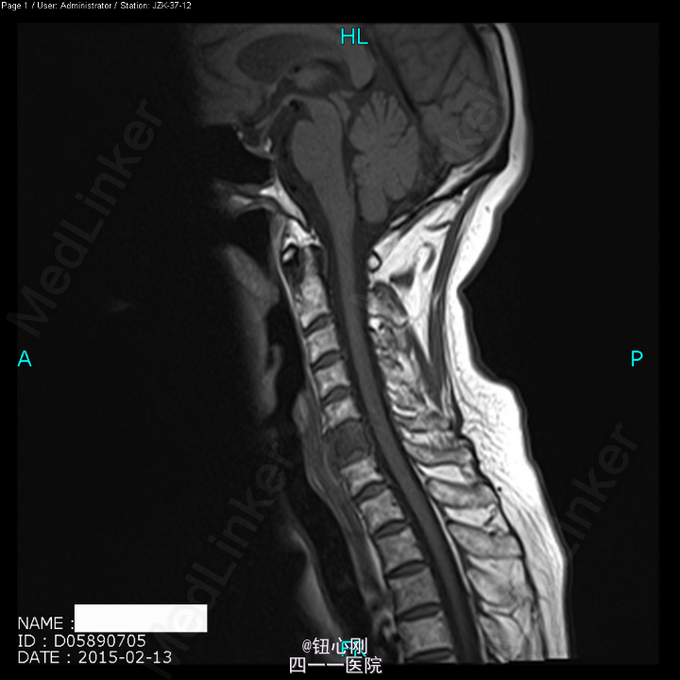

体检未见明显阳性体征。 辅助检查:血沉68mm/h,神经元特异性烯醇化酶23ug/l,余肿瘤指标正常。三大常规、肝肾功、电解质正常。 颈椎MRI、腰椎MRI及PET-CT扫描见图。

术前诊断:多椎体病变待查(转移瘤?) 诊断依据:老年女性,出现颈腰部疼痛,MRI及PET-CT扫描提示椎体多节段病变,以转移瘤可能性为大,同时血沉升高。 处理:2015-03-31在全麻下行颈6椎体病变前路次全切+钢板钛网植骨融合内固定术。术中所见:颈6椎体骨质疏松,部分硬化,未见鱼肉样组织。术后切除骨质送病理检查。 病理报告:骨小梁稀疏,其间有纤维组织,同时可见硬化死骨。 术后诊断:颈6椎体骨质疏松性骨坏死。

随着医学影像学及脊柱微创手术的发展,骨质疏松性椎体骨坏死逐渐被认识。该病临床上并非少见,骨坏死会导致椎体逐渐塌陷与进行性后凸畸形,引起患者长期腰背痛,甚至出现脊髓神经受压而瘫痪。患者为老年,主诉脊柱疼痛,MRI有椎体信号改变,因而易与脊柱转移性肿瘤混淆。骨坏死椎体在T1WI加权像上呈界限清楚的低信号区域,在T2WI加权像及脂肪抑制序列像上呈界限清晰高信号区域。这是与脊柱转移性肿瘤相鉴别的要点,对于累计整个椎体的骨坏死更需注意鉴别。 如疼痛不缓解或发生后凸畸形,可行椎体后凸成形术。